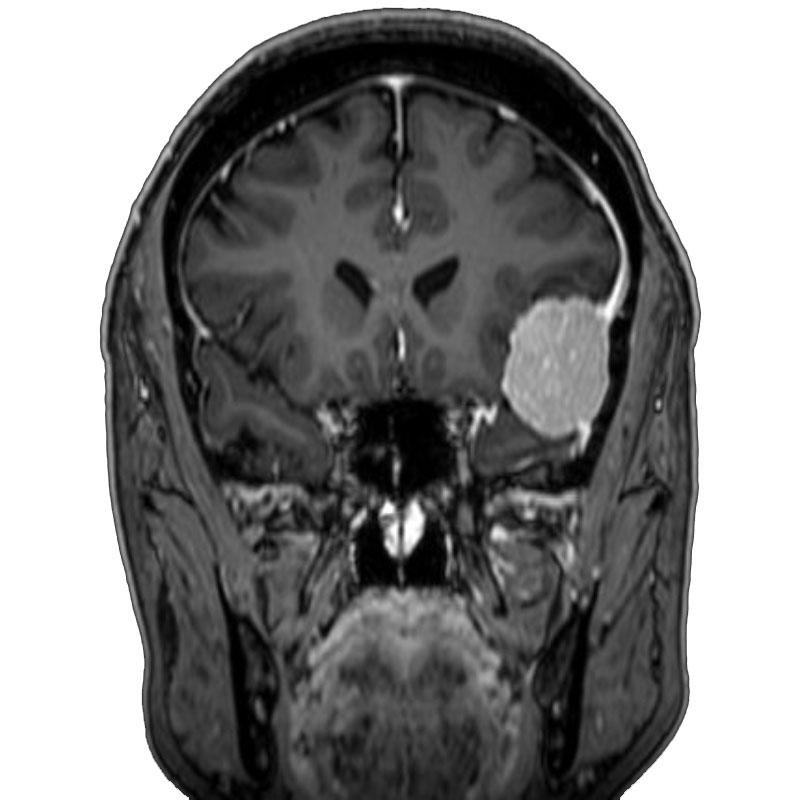

右側頭葉脳腫瘍

摘出術

南田/野本/佐伯